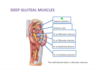

Deep Gluteal Region

Identify.

Gluteus minimus

34

Identify.

Piriformis

35

Identify.

Superior gemellus

36

Identify.

Obturator internus

37

Identify.

Inferior gemellus

38

Identify.

Quadratus femoris

39

Identify.

Gluteus minimus

40

Identify.

Piriformis

41

Identify.

Superior gemellus

42

Identify.

Obturator internus

43

Identify.

Inferior gemellus

44

Identify.

Quadratus femoris